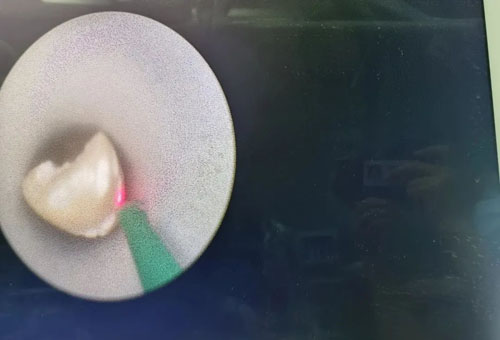

經皮腎鏡鈥激光碎石取石中

在程廣舟副院長的指導下,程波副主任為患者實施手術。患者結石質地堅硬,碎石困難,在麻醉醫(yī)師與手術室護士的通力配合下,該患者順利完成雙側“無管化”經皮腎鏡碎石取石術。從精準穿刺到擴張,再到手術結束,僅僅用了1個半小時。手術過程中,麻醉醫(yī)生密切觀察患者情況,術后患者順利復蘇,術后恢復良好,未出現發(fā)熱情況,術后復查腹部平片未見結石殘留,患者及家屬非常滿意。